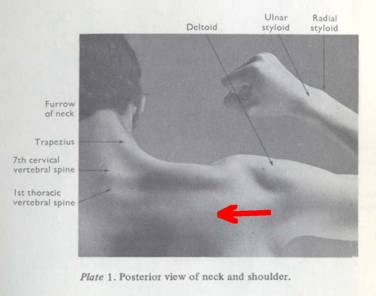

The Back Wound

In the autopsy photograph (Appendix 5, Figure 2), the back wound appears to lie at about T1 (i.e., the first thoracic vertebra), just above the level of the scapular spine. This seriously disagrees with the T3 on the death certificate, which was prepared by Admiral Burkley (p. 221). Two individuals even placed it at T4: James Jenkins and, in a conversation with me, John Ebersole (who practiced my specialty of radiation oncology). For normal anatomy see Appendix 5, Figures 3A and 3B. As is well known, the back wound in the autopsy photo is noticeably higher than the holes in the shirt or jacket. Furthermore, the wound on the Autopsy Descriptive Sheet (prepared by Boswell at the autopsy; see Appendix 5, Figure 4) appears to lie well below T1—at least as low as T2, if not even lower. An online source assigns a typical level to the scapular spine as T3 (manualmed.blogspot.com/2008/09/thoracic–spine-landmarks.html). In fact, any level for this back wound below T1 would destroy the SBT (because the back wound would then be lower than the throat wound). However, Boswell later elevated this wound, thus abandoning his earlier, on-site observation. Somewhat amusingly, on this second occasion Boswell elevated this back wound far too high (compared to the autopsy photo), actually into the neck, which only raises questions about either his memory or his honesty. (See these two incompatible placements by Boswell at Inside the ARRB by Douglas Horne, Volume I, Figure 56.) A likely explanation for the discrepancy between the photo and the Descriptive Sheet is post-autopsy (illicit) photo alteration in the dark room. Curiously, this is the precise autopsy photo that displays an anomalous object on the back (not noted by prior investigations), which might be a leftover image from photographic tampering. Further discussion of this follows below.

Another point is worth emphasizing: physical tests showed no copper deposits on the shirt or on the collar (in the front), even though they were present on the back of JFK’s jacket. This is consistent with a metal projectile as the source for the back wound, but it is inconsistent with a metal projectile through the front of the shirt. On the contrary, the slits had probably been created by the nurses’ scalpels. In an interview in 1971, Carrico actually confirmed this to Harold Weisberg—see Weisberg’s Subject Index File, under “Carrico,” items 02 and 03. (Jerry McKnight reports this.) In addition, based on my personal observations at the Archives, some cloth is missing from both the back of the shirt and the back of the jacket, but none appears missing from the slits at the collar. Furthermore, although McAdams claims that a throat wound at C7/T1 is feasible, he totally ignores the anatomic conundrums in the horizontal plane. (For pertinent, and rather devastating, anatomy and radiology images see Appendix 5, Figures 5-7.) For a more precise vertical level for the throat wound see MIDP (p. 228). James H. Fetzer has also offered a concise analysis of this evidence in “Reasoning about Assassinations,” which he presented at Cambridge and then published in an international, peer-reviewed journal (The International Journal of the Humanities (2005-2006), Volume 3, Issue 10, pp. 31-40).